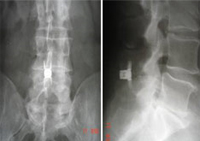

Izquierda: escáner de control post-operatorio de la caja intersomática PEEK

colocada por técnica percutánea. Derecha: doble fusión intervertebral con caja

de PEEK con incisiones de solo 12 mm y bajo anestesia local